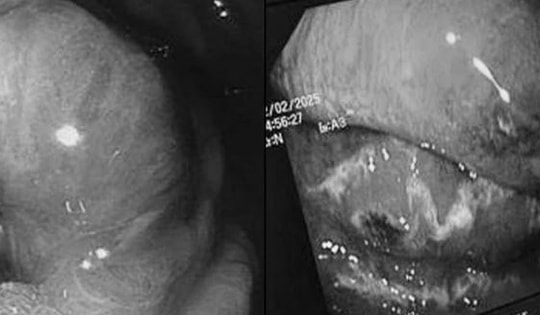

Nuốt nhầm hạt nhót, cụ bà nguy kịch

Cụ bà nhập viện trong tình trạng đau bụng dữ dội, bụng chướng, sốt và mệt mỏi. Qua thăm khám và các xét nghiệm cận lâm sàng, bác sĩ phát hiện dị vật trong đường tiêu hóa đã gây thủng trực tràng và viêm ổ bụng.